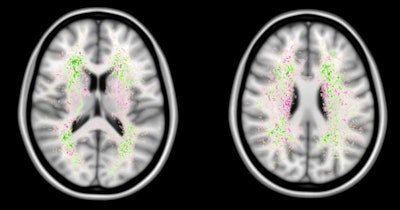

False negatives are the most common source of error for both humans and computers. The images show a spatial distribution of the false-negative white-matter hyperintensity segmentations of a human observer and the top 4 ranking methods in the WMH Segmentation Challenge. The colors indicate the differences. Green means that the top 4 methods had fewer false negatives, while pink means that the human observer had fewer false negatives. Overall, the top 4 AI methods had fewer false negatives than a human observer, but the AI methods made more mistakes at locations where lesions are rarely found. Images courtesy of Hugo Kuijf, PhD.